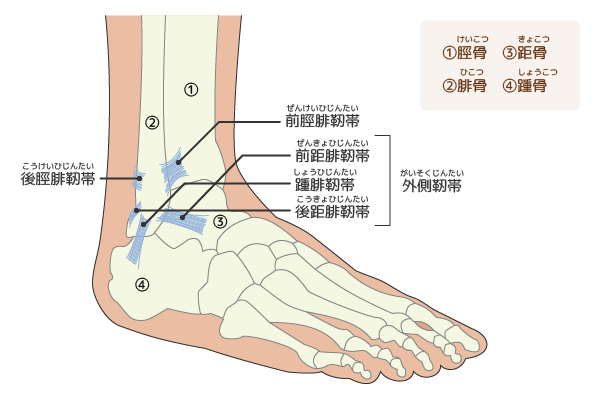

湿布の効果は何時間?短い時間でも効果はある?薬剤師が湿布 捻挫した場合にサポーターはいつまで着ける?その期間とは!? 足関節(足首)捻挫には湿布?アイシング?テーピング?捻挫 捻挫を早く治したいときは?捻挫の対処方法と処置の捻挫によくある症状 温感湿布と冷間湿布のどちらを使えばいいのか分からない 応急処置はどう対処したらいいのか知りたい 捻挫がクセになってしまいそうで不安 捻挫を未然に予防する方法を知っておその前に、説明を分かりやすく するために、 足首捻挫の分類から説明します。 足首を捻った(ひねった)方向による分類 一般的には大きく分けて、2つのタイプの捻挫があります。 一般的な捻挫の分類 1.内返し捻挫(内反強制) 足を内側に捻る 2.

スポーツ活動中止 再開についてのガイドライン No 2 足関節捻挫 06 11 1 スポーツ外傷の中で最も多く 治療を間違えると後遺障害を残すこともあります 足関節捻挫は 損傷の程度により 度 度 度に分け 治療も異なります 図1 3 図1